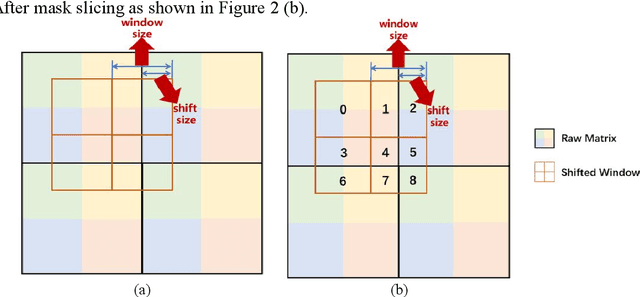

With the development of computer technology, various models have emerged in artificial intelligence. The transformer model has been applied to the field of computer vision (CV) after its success in natural language processing (NLP). Radiologists continue to face multiple challenges in today's rapidly evolving medical field, such as increased workload and increased diagnostic demands. Although there are some conventional methods for lung cancer detection before, their accuracy still needs to be improved, especially in realistic diagnostic scenarios. This paper creatively proposes a segmentation method based on efficient transformer and applies it to medical image analysis. The algorithm completes the task of lung cancer classification and segmentation by analyzing lung cancer data, and aims to provide efficient technical support for medical staff. In addition, we evaluated and compared the results in various aspects. For the classification mission, the max accuracy of Swin-T by regular training and Swin-B in two resolutions by pre-training can be up to 82.3%. For the segmentation mission, we use pre-training to help the model improve the accuracy of our experiments. The accuracy of the three models reaches over 95%. The experiments demonstrate that the algorithm can be well applied to lung cancer classification and segmentation missions.